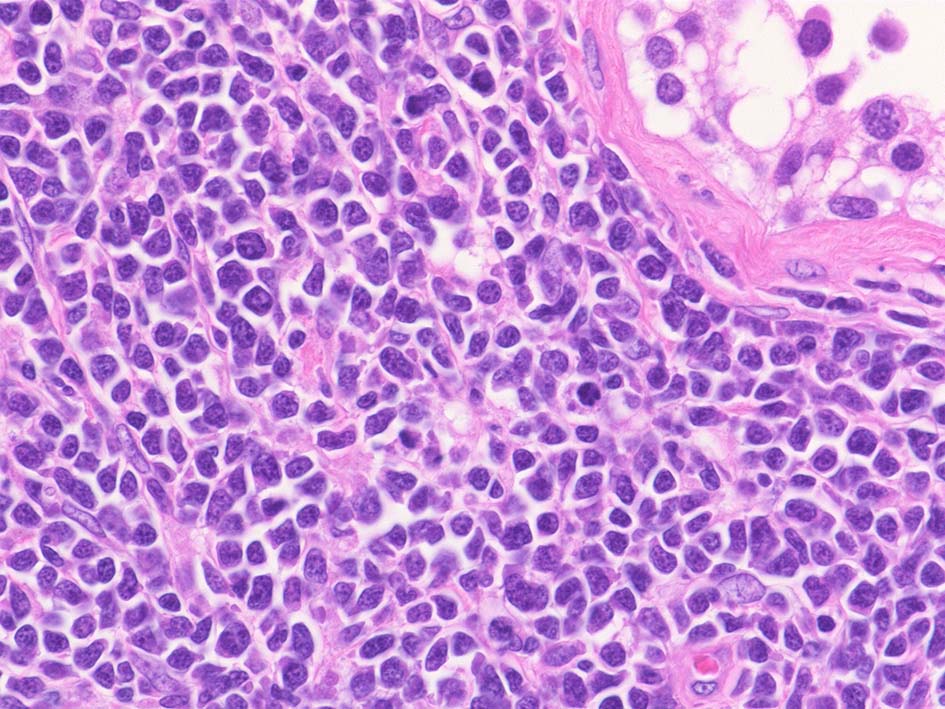

増殖巣では精細管は消失, 萎縮. 腫瘍境界部での浸潤所見がある.

精細管の多くがスペアされ, 間質にlymphoid cellsが密に浸潤している. わずかな精細管に浸潤が認められ萎縮や破壊像が認められる. 精細管において Lymphoepithelial lesion(LEL)に似た所見がある.